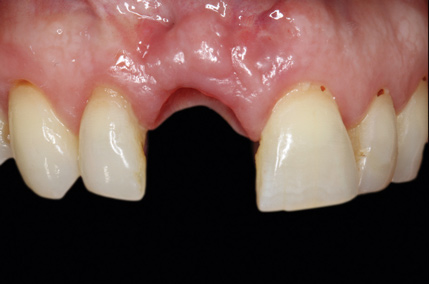

(13.) Postoperative image of site No. 8 taken 4 months after extraction and grafting.

Figure 13